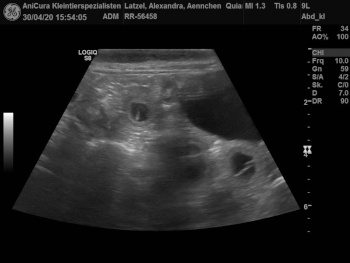

Aennchen und Tessa sind Schwanger! Hier sind die Ultraschallbilder !!! |

| Die Ultraschallbilder von Aennchen von Waltenweiler!!! |

| Die Ultraschallbilder von Tessa von Waltenweiler!!! |